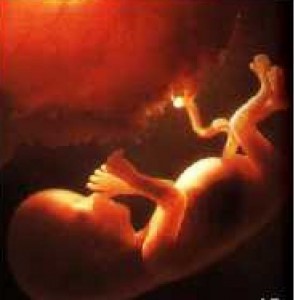

20 haftalık bebek Bebeğinizin cildi sürekli sıvı ortama maruz kaldığı için vernix caseosa adı verilen madde ile koruma altına alındı. 20 cm. ve saçları hızla uzamaya devam ediyor.

Gittikçe büyüyen rahminiz nedeniyle hafif ağrılarınız ve kramplarınız olabilir ama yakında hepsi geçecek.